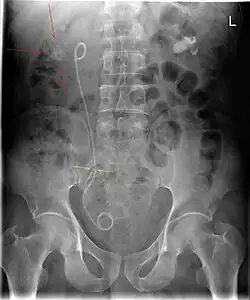

Nierstenen kunnen bestaan uit een aantal verschillende verbindingen. De meest voorkomende is calciumoxalaat. Het gebruik van veel calcium in het dieet leidt overigens niet tot een hoger niersteenrisico. Het is zelfs zo dat mensen met nierstenen gemiddeld minder calcium gebruiken dan mensen zonder nierstenen. De reden is waarschijnlijk dat calcium in de darm oxalaat bindt dat dan vervolgens niet meer door het lichaam wordt opgenomen. Calciumhoudende stenen zijn op de gewone röntgenfoto van de buik meestal waarneembaar; dit geldt niet voor alle stenen. Andere stoffen waaruit nierstenen kunnen bestaan zijn struviet, calciumfosfaat, urinezuur en cystine (alleen bij mensen met de ziekte cystinurie). Struvietstenen ontstaan meestal in aanwezigheid van een bepaalde bacterie (vooral Proteus mirabilis) die ureum omzet in ammoniak en koolstofdioxide (ammoniumcarbonaat).

Vaak zijn de klachten samen met het aantonen van bloed in de urine voldoende om de diagnose te stellen. Er zijn echter meer ziekten die zich op een vergelijkbare manier presenteren. Als de klachten en het bloed in de urine in de loop van ongeveer een week niet verdwijnen wordt vaak een echo gemaakt van de nieren om te zien of de steen nog aanwezig is of dat er een andere reden gevonden kan worden voor de klachten. Tegenwoordig wordt er bij nierstenen geen IVP meer gemaakt, een CT-scan van de buik is hiervoor beter geschikt.